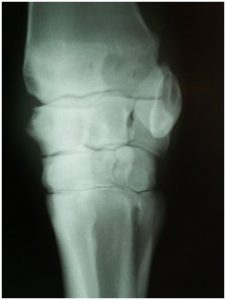

- Diagnostic imaging- radiography or ultrasound

- Radiography, ultrasound

Waverly Equine Services has a top of the line portable digital x-ray system allowing for instant high-quality x-ray images. Digital radiography is one of several valuable diagnostic tools that allow an equine veterinarian to see changes inside your horse. X-rays are commonly used in diagnosing causes of lameness such as navicular disease, OCD, and osteoarthritis. They are also used to diagnose conditions such as tooth abscesses, sinus infections, kissing spine, cervical arthritis and much more. Radiography has been fundamental in equine diagnostic imaging for years and digital radiography takes it to another level.